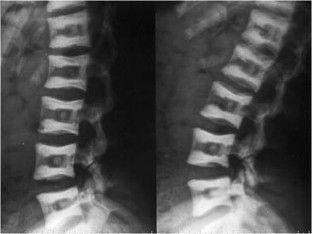

Atypical, unusual, and misleading imaging presentations of spondylolysis

Although lumbar spondylolysis is a widely known and easily recognizable condition in its typical presentation, there are some less well-known forms that may occasionally be challenging and/or demand special attention on imaging. Examples include: acute and/or incomplete lesions; unilateral defects; lesions at unusual levels (cervical, upper lumbar, and multi-level spondylolyses); iatrogenic lesions; non-isthmic spondylolysis; and spondylolysis related to underlying diseases. In addition to their atypical, uncommon or confusing imaging presentations, these forms of spondylolysis are far rarer than the classic type and have been described, to a great extent, in the surgical literature, thus reducing the awareness of radiologists about them and raising the potential for misdiagnosis and inadequate treatment. In this review the authors address these special manifestations of spondylolysis, stressing the more important features to be considered in the differential diagnosis and the impact of a precise diagnosis of spondylolysis on the patient’s care.